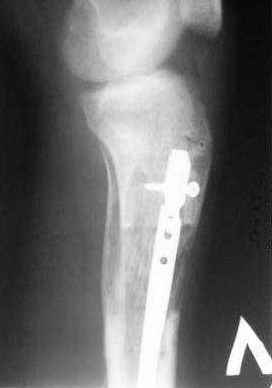

Пациент 19 лет, производственная травма, придавлен тяжелой плитой. Политравма (ISS 21).

1 - рентгенограмма (прошу прощения за качество) при поступлении;

2 - внешний вид голени;

Произведено ПХО, acute shortening (5 см), фиксация стержневым аппаратом Hoffman.

3,4 - через 4 недели наложен спице-стержневой аппарат, произведена остеотомия большеберцовой кости в верхней трети, раны зажили, проводилась дистракция в аппарате.

5, 6 - через 2,5 мес после травмы выполнен закрытый остеосинтез блокируемым штифтом.

7, 8, 9, 10, 11 - через 8 мес после травмы перелом сросся.

Пациент ходит без дополнительной опоры, не хромает (видеоролик выложил сюда

http://rapidshare.com/files/14134274/Patient_B.AVI.html, вес 892 кб).